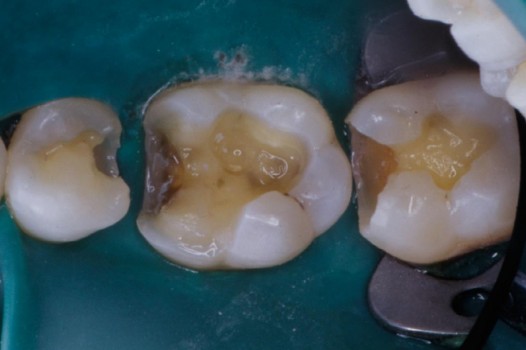

Traditional amalgam (mercury) fillings have been used for over a century, but concerns about health risks, tooth fractures, and long-term decay have led many dentists to adopt modern alternatives. Today, metal-free restorations offer healthier, stronger, and more natural-looking results.

Using advanced resins, ceramics, and state-of-the-art bonding techniques, Dr. Klim can restore teeth with precision, preserving healthy tooth structure while preventing fractures, bacterial invasion, and future toothaches.